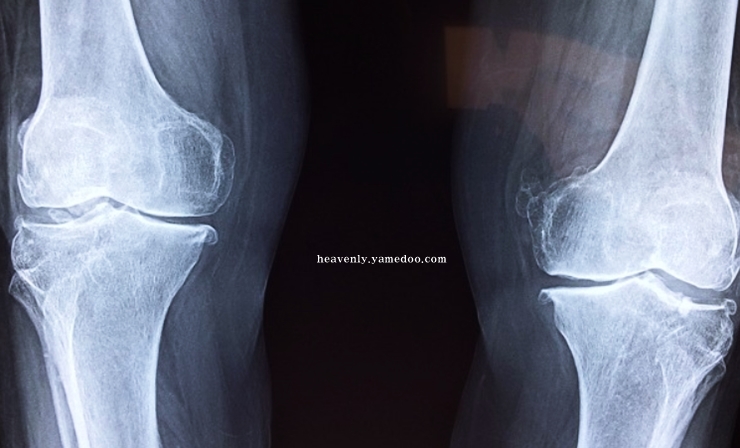

반월상 연골판이란, 무릎 관절 사이사이에 있는 반달 모양의 물렁뼈입니다. 우리의 체중을 견디는 작용을 하는 부위입니다. 무릎 안쪽과 바같쪽에 양쪽에 하나씩 있습니다. 뼈와 뼈가 부딪힐 때 손상되지 않도록 하거나 완충효과를 가지고 오는 것이 바로 반월상 연골판입니다.

무릎에서 쿠션 역할을 하는 반월상 연골판이 파열되면 뚝뚝하고 무릎에서 소리가 나게됩니다. 또 무릎이 삐걱대거나 뻑뻑한 느낌이 듭니다. 반월상 연골판에 문제가 발생하면 조금만 걸어도 통증이 나타나고 경사로 또는 계단을 오를 때 갑자기 다리에 힘이 풀려 주저앉는 일이 발생할 수 있습니다.

만약 연골판 손상을 방치하면 퇴행성 관절염으로 발전할 수 있습니다. 반월상 연골판이 제 역할을 하지못해 각종 부위에 손상이 발생되면 무릎에 있는 관절을 보호하는 기능을 하지 못해 무릎을 구부리거나 움직일 때 심한 통증을 초래하기 때문입니다. 반월상 연골판의 중요성을 다시 한 번 깨닫게 되었습니다.

무릎통증 원인 초기에는 단순한 타박상으로 오인할 수 있습니다. 그런데 치료하지 않고 방치하면 뼈와 뼈가 서로 맞닿으며 퇴행성 관절염을 불러옵니다. 반월상 연골판은 혈관이 존재하지 않아 한 번 손상되면 자연적인 치유 또는 재생이 어렵운 신체부위입니다.